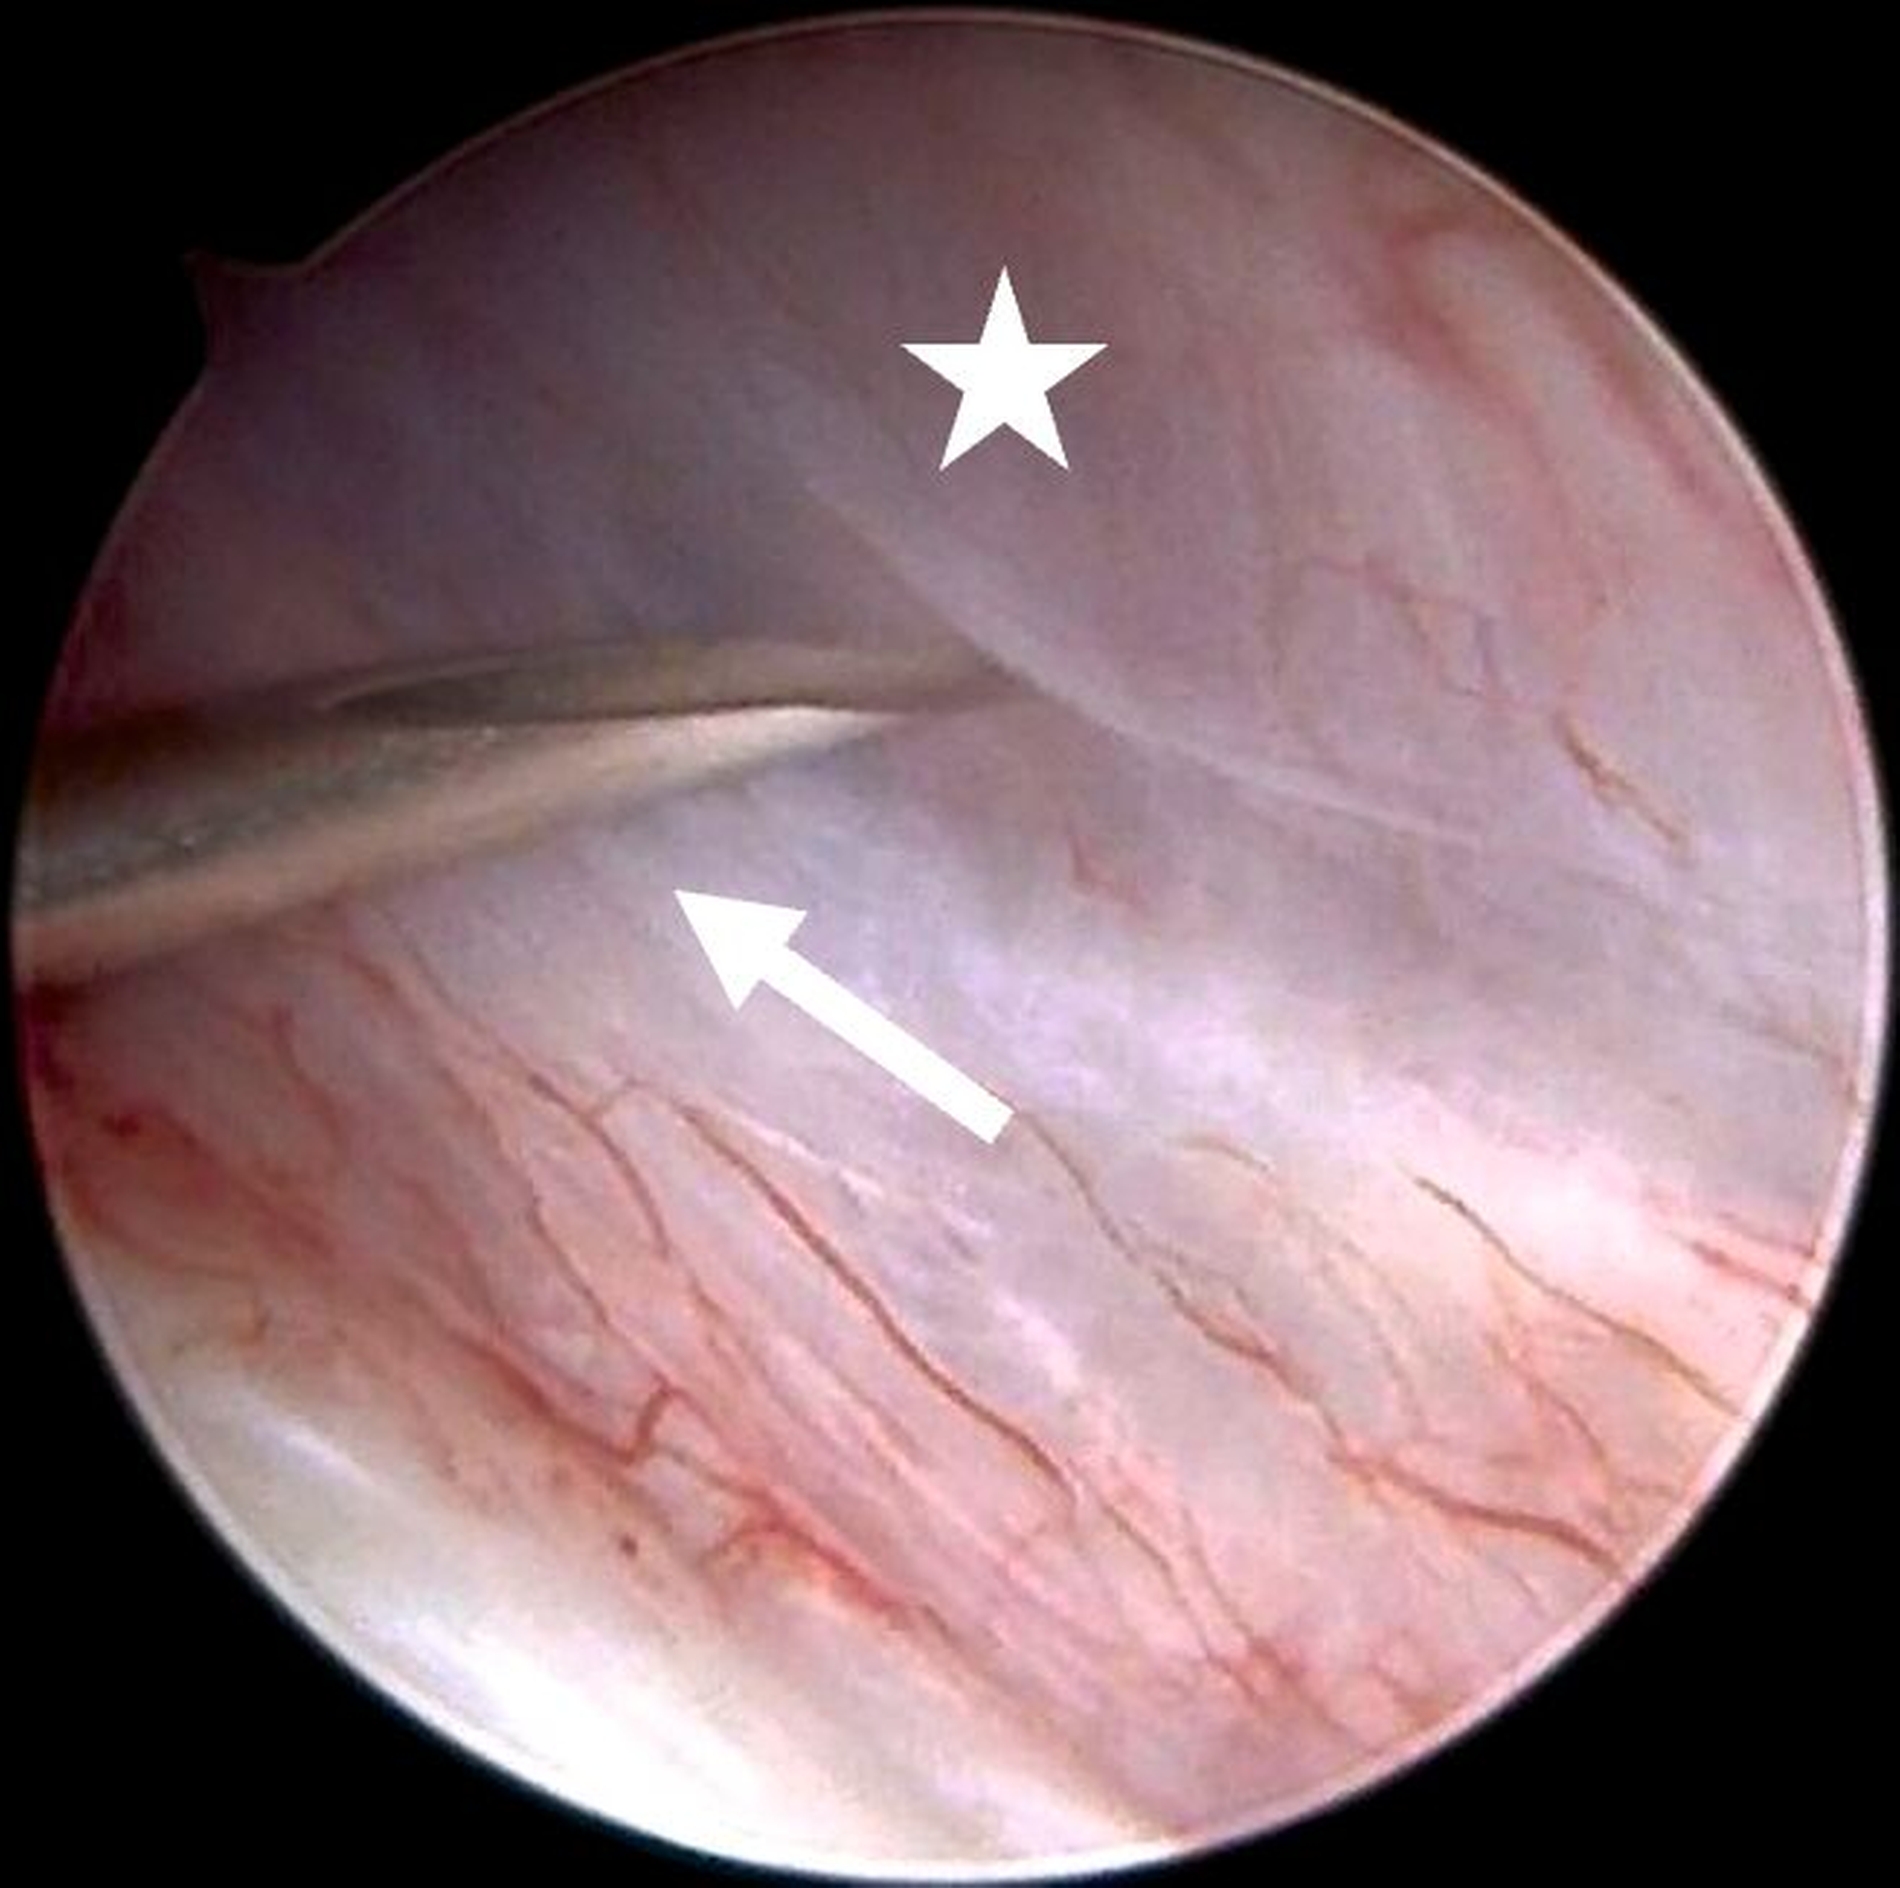

Für die Kiefergelenksarthroskopie ist eine strukturierte Orientierung innerhalb des oberen Gelenkkompartiments essenziell. Hierfür haben sich die sogenannten „seven points of interest“ nach McCain etabliert (Abbildung 3) [Srouji et al., 2018]. Diese sieben anatomischen Referenzpunkte dienen der systematischen Beurteilung des Gelenks während des arthroskopischen Eingriffs. Zunächst werden das mediale synoviale Band und der Pterygoid-Schatten („pterygoid-shadow“) als Orientierungspunkte identifiziert. Es folgen die bilaminäre Zone – eine häufige Schmerzquelle – sowie die hintere Schräge der Gelenkeminenz. Die Beurteilung des Discus articularis gibt Auskunft über Verlagerungen und degenerative Prozesse. Es folgt die Beurteilung der intermediären Zone, die besonders anfällig für eine Perforation ist. Abschließend erfolgt die Begutachtung des vorderen Recessus. Dieser stellt den Eintritt der Punktionsstelle des Level-II-Zugangs dar [Srouji et al., 2018].